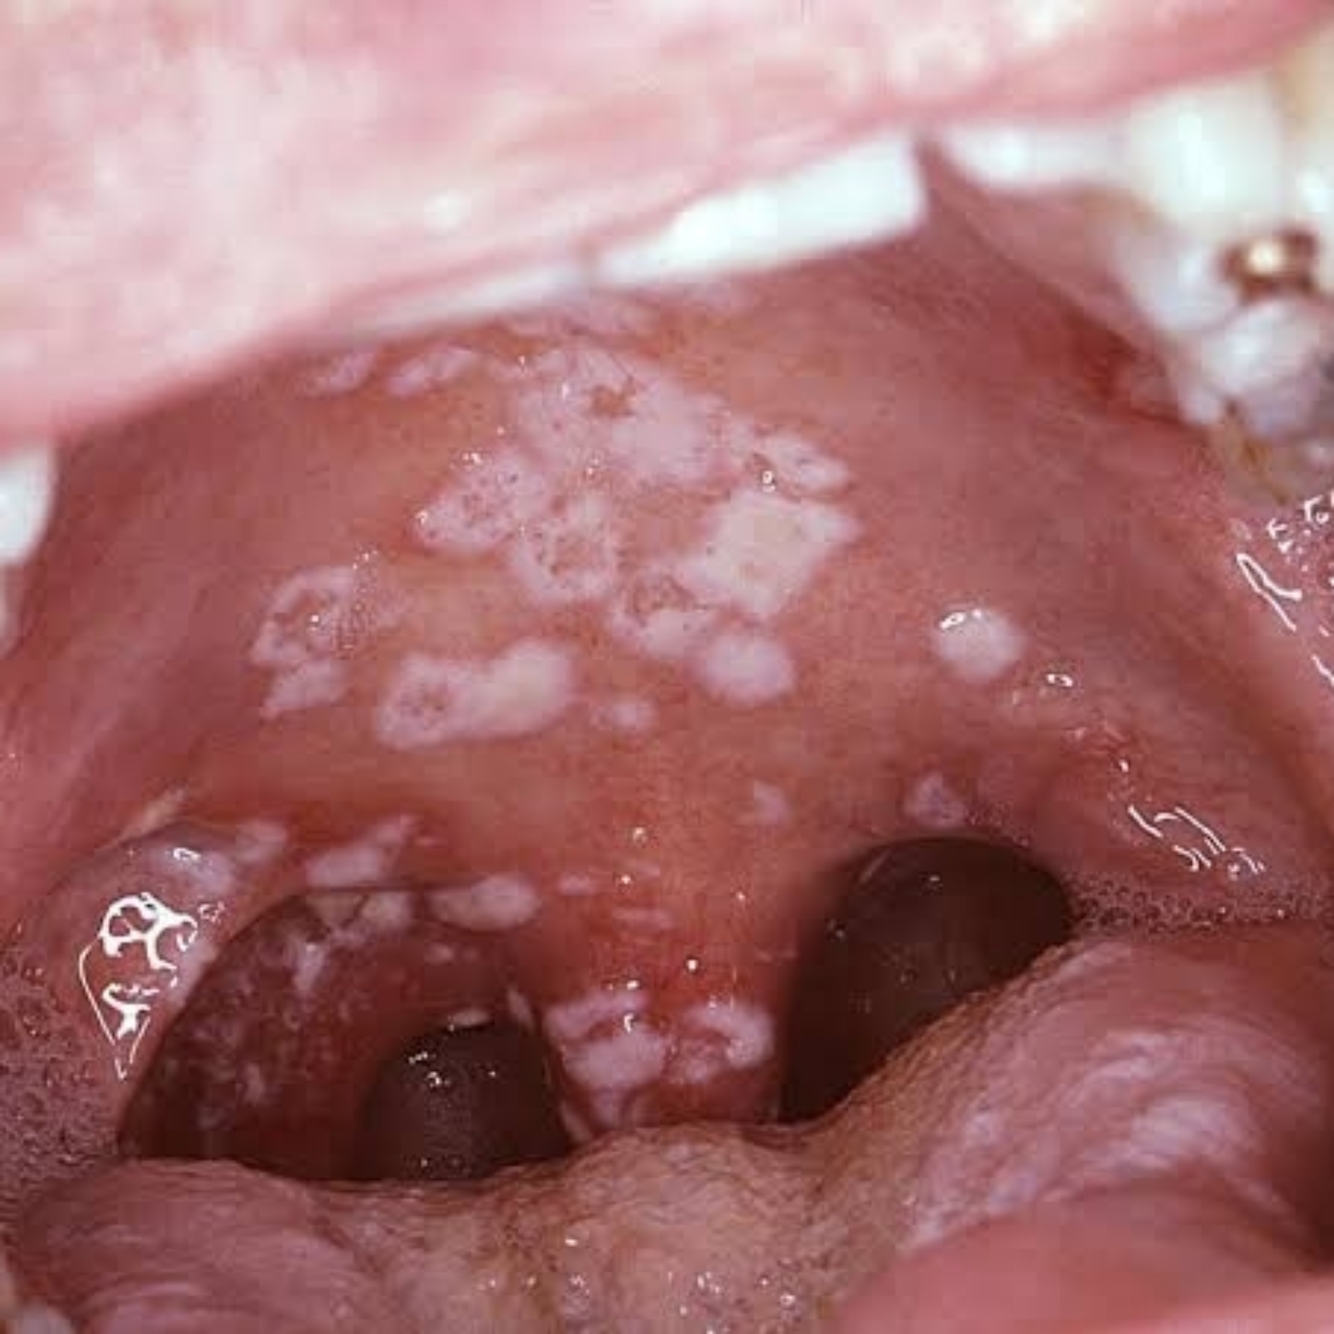

• Candidíase Oral :

Placas brancas em mucosa oral

Halitose

Ardência

Odinofagia

Disfagia

Uso Oral :

1 . Miconazol 2 % gel oral (Daktarin ) – 40g

- Aplicar 1/4 de colher de chá (1,25 ml ) nas lesões da boca , 6/6h , até 1 semana após desaparecer lesões .

- O gel deve ser mantido na boca pelo maior tempo possível

- Higienizar a boca com uma colher de chá de bicarbonato de sódio e um copo de água .